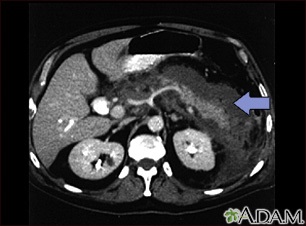

Acute pancreatitis is sudden swelling and inflammation of the pancreas.

The following imaging tests that can show swelling of the pancreas may be done, but are not always needed to make a diagnosis of acute pancreatitis: